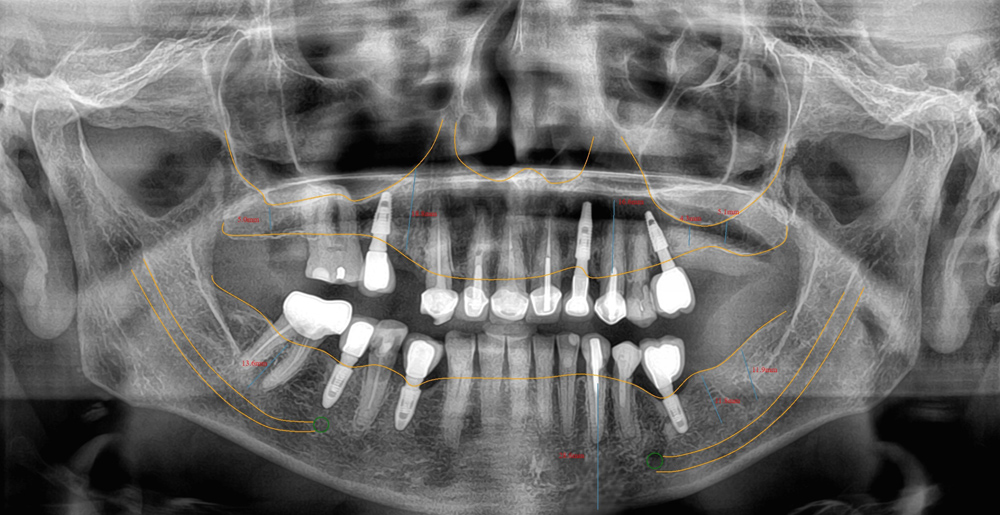

Panorâmica com traçado para implante;